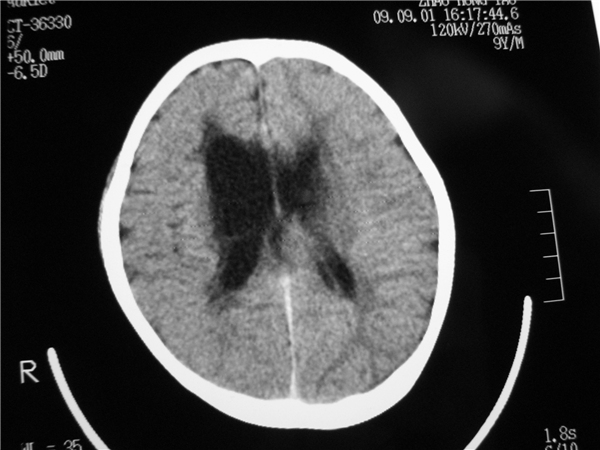

以下是引用余辉在2009-9-2 8:06:00的发言:[br]右侧侧脑室扩大,脑髓质量明显减少,胼胝体区结构不良,脑沟增深。考虑右侧大脑萎缩伴胼胝体发育不良(可能后遗改变(hie史?)),请查病史。第三脑室四脑室扩张,应该有脑积水存在

以下是引用dyqct在2009-9-1 21:57:00的发言:[br]右侧侧脑室扩大,脑髓质量明显减少,脑沟增深。考虑右侧大脑萎缩(可能后遗改变),请查病史。

以下是引用拾荒者在2009-9-2 20:53:00的发言:[br]右侧侧脑室扩大,脑髓质量明显减少,胼胝体区结构不良,脑沟增深。考虑右侧大脑萎缩伴胼胝体发育不良。至于是否合并脑炎,可结合实验室检查或脑脊液检查。